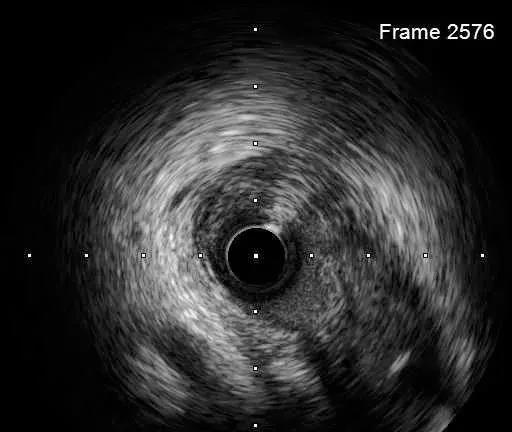

IVUS-1

远段直径2.2*2.4mm

对角支处局限血肿